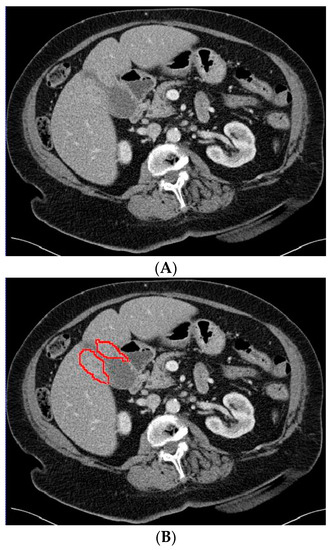

The 3D portal venous phase CT scans were pre-processed before being fed to the deep learning model. To improve contrast among abdominal organs, the CT scans were processed by a soft window centering at 50 HU with a width of 400 HU. To normalize the CT scans throughout the entire dataset, the images were resampled to the same spacing of 1.0, 1.0, and 2.0 by a linear interpolator. Using the software ITK-SNAP, the gallbladder on the CT scans was manually delineated by an abdominal radiologist who was blinded to the final diagnosis. Examples of the CT scans with segmented GBC and benign gallbladder disease can be found in Figure 2 and Figure 3.

Figure 2.

Axial CT slice (A) with an example of gallbladder cancer (histopathologically proven adenocarcinoma, encircled in (B)) and subsequent segmented gallbladder (C).